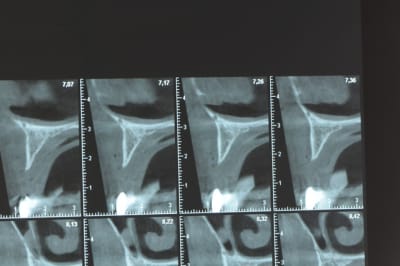

voili, voila...

avant de faire la tomosynthèse je comprenais pas pourquoi j'avais aussi peu de contraste.

Ce n'est pas vraiment un consensus mais plutot du bon sens. Si tu as une crête en profil de lame de couteau cela signifie que tu as une fusion des corticales vestibulaire et palatine et donc absence de spongieux, ce qui comme tu le sais n'est pas indiqué en implanto (cj os de marbre par exemple)

Il me semble que Palti ou encore Szmukler-Moncler recommandent un minimum de 2-3mm. Si c'est plus fin, greffe d'apposition et GBR.

Dans ton cas il te faudrait abaisser la crête de 3 bons mm pour arriver à cette épaisseur.

Ce n'est pas vraiment un consensus mais plutôt du bon sens. Si tu as une crête en profil de lame de couteau cela signifie que tu as une fusion des corticales vestibulaire et palatine et donc absence de spongieux, ce qui comme tu le sais n'est pas indiqué en implanto (cj os de marbre par exemple)

Il me semble que Palti ou encore Szmukler-Moncler recommandent un minimum de 2-3mm. Si c'est plus fin, greffe d'apposition et GBR.

Dans ton cas il te faudrait abaisser la crête de 3 bons mm pour arriver à cette épaisseur.